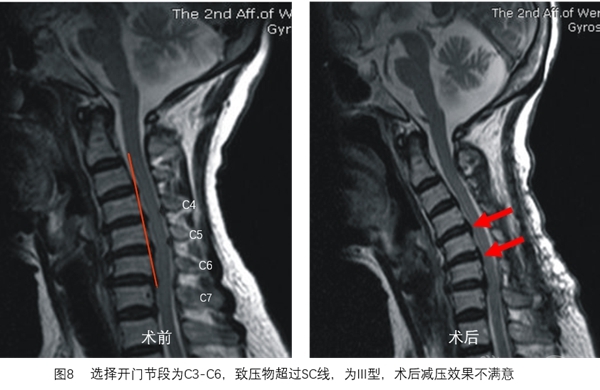

SC线同时反映颈椎管曲度、脊髓曲度与致压物的关系,根据SC线及其分型能更好地预测颈椎开门椎管成形术后脊髓减压的效果(图3~图8)。

对于压迫严重的节段(SC线III型),即使扩大减压范围也无法获得满意的减压效果的,需要对该节段进行前路二次手术,术后可获得满意的减压效果(图10~图11)。

选择开门节段后,划出SC线,分型为I型开门术后减压满意,II型大部分可获得减压,III型减压不满意。